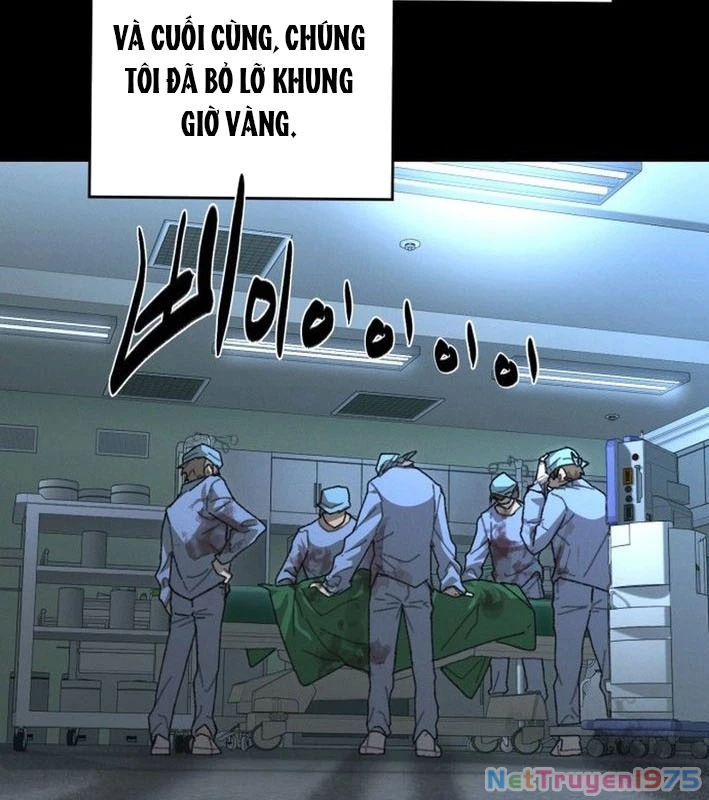

Kẻ Chôn Cất Quái Vật - Chapter 1